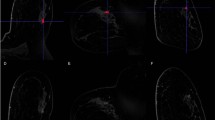

Eighty-six consecutive women with 86 DCIS lesions diagnosed by biopsy underwent UF-MRI including pre- and 18 post-contrast ultrafast scans (temporal resolution of 3 s/phase). The last phase of UF-MRI was used to perform 3D segmentation. The time point at 6 s after the aorta started to enhance was used to obtain subtracted images. From the 3D segmentation and subtracted images, enhancement, shape, and texture features were calculated and compared between low- and non-low-grade or upgrade DCIS lesions using univariate analysis. Feature selection by least absolute shrinkage and selection operator (LASSO) algorithm and k-fold cross-validation were performed to evaluate the diagnostic performance.

Surgical specimens revealed 16 low-grade DCIS lesions, 37 non-low-grade lesions and 33 upgrade DCIS lesions. In univariate analysis, five shape and seven texture features were significantly different between low- and non-low-grade lesions or upgrade DCIS lesions, whereas enhancement features were not. The six features including surface/volume ratio, irregularity, diff variance, uniformity, sum average, and variance were selected using LASSO algorism and the mean area under the receiver operating characteristic curve for training and validation folds were 0.88 and 0.88, respectively.